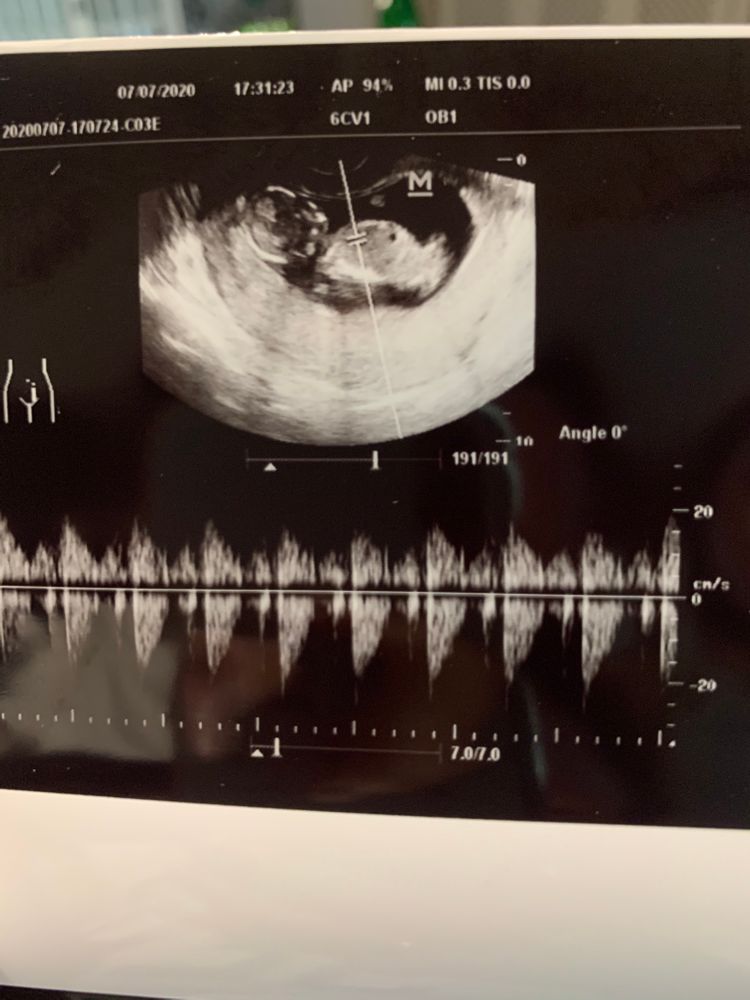

Мальчик???

Девочки посмотрите пожалуйста 😇 Завтра уже 19 недель и не знаю кто будет у нас... но сегодня присмотрелась на узи которое делали в 14 недель.

Ставлю на мальчика, так как похоже на фото все таки половой бугорок и он смотрит вверх. А ещё замечала, что мальчишки пузатенькие, у вашего такой кругленький животик.

По картинке сложно понять ибо это может пуповина лежать, может ручка.

Плюс половые бугорки у них похожи, только у девочек под другим чуть углом. Поэтому, лучше ещё сходите к хорошему сонологу. Или уже подождите второго скрининга)